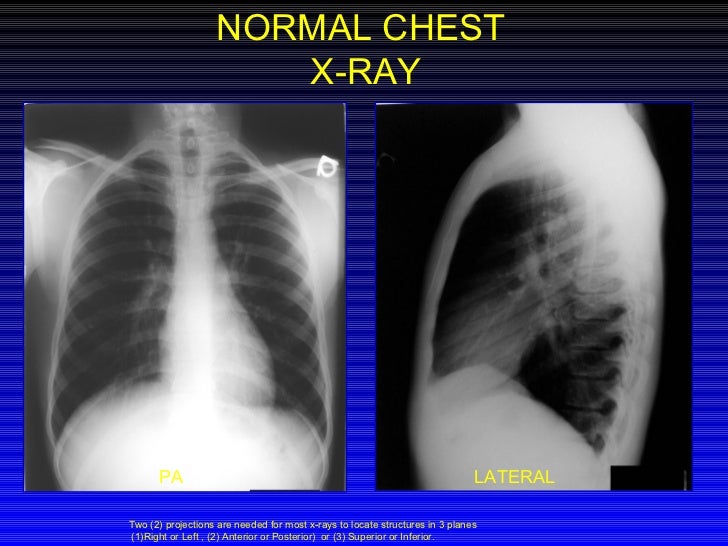

Normal Chest X Ray Images

CHEST X RAY ANATOMY AND PROJECTIONS EVALUATING CHEST Difference Between 1 View And 2 View Chest X Ray Figure 1 radiographs and line diagrams. The interpretation of a chest film. Which one is ap and which one is pa? The difference between chest posterior anterior (pa) and anterior posterior (ap) radiographs. This will provide the most. On the pa view, the cardiac borders are smaller and more defined. In fact every radiologst should be an expert in chest. Difference Between 1 View And 2 View Chest X Ray.